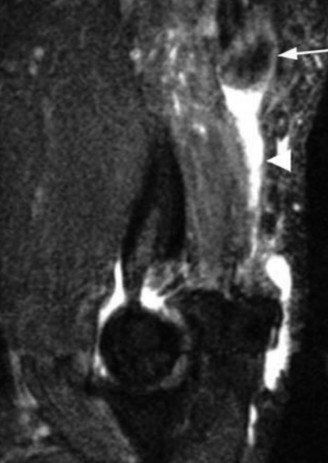

While plain films confirm the presence of osseous reactive changes, Magnetic Resonance Imaging (MRI) is indispensable for evaluating the articular cartilage, the integrity of the UCL, and the presence of occult loose bodies. A high-resolution MRI, preferably an MR Arthrogram (MRA) if subtle UCL pathology is suspected, provides a comprehensive map of the elbow's soft tissue envelope.

In this case, the MRI demonstrates focal chondromalacia and subchondral edema at the posteromedial olecranon tip and the corresponding medial wall of the olecranon fossa—the classic "kissing lesion" of VEO. Crucially, the anterior bundle of the UCL appears continuous and intact, with no evidence of high-grade partial tearing, T-sign (contrast leakage beneath the distal insertion), or severe attenuation. The flexor-pronator mass and the ECRB origin are pristine.